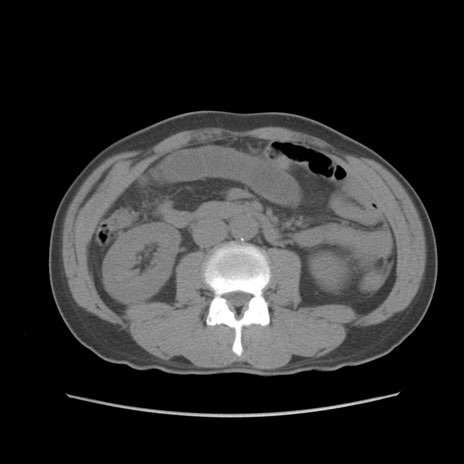

症例56 CT(横断像)

脂肪ウインドウ